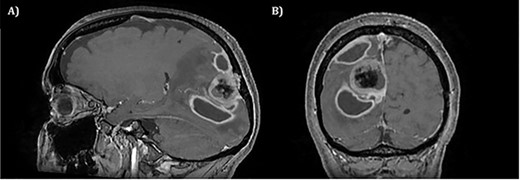

Two weeks later, whilst awaiting surgery, she attended the Emergency Department with a fever of 38.6°C and mildly raised inflammatory markers (WCC 10.4, Neut 8.4). Urine dip and CXR were unremarkable. The source of the infection was not isolated and the emergency medicine physicians discharged her with a course of empirical oral antibiotics. The neurosurgical team were not made aware of this attendance. Twelve days later, she underwent a planned neuronavigation-planning MRI scan as an outpatient. This was arranged one week prior to the scheduled surgery, in line with our departmental protocol. The MRI was reviewed and two new rim-enhancing collections superior and inferior to the tumour were noted, associated with extensive perilesional oedema (Fig. 2A and B). The patient was then immediately contacted via telephone and reported new worsening of headaches and new right sided weakness. She was admitted to hospital directly for assessment and emergency treatment. Her inflammatory markers on admission had risen to a WCC of 19.5, Neut 16.6, but CRP was <1. She was started on an emergency steroid treatment and subsequently underwent craniotomy, total resection of the meningioma and drainage of the intraparenchymal paratumoural abscesses. Intra-operatively the brain was swollen; pus collections were encountered in abscess cavities superior and inferior to the solid tumour, which had a necroticcore.

T1 weighted MRI postgadolinium enhancement in both sagittal (A) and coronal (B) views. There are two new rim-enhancing cystic lesions. A superior lesion of 31.4 mm as measured on the coronal reconstructed images and is abutting the adjacent dura of the right parietal lobe and is sited superior and lateral to the right occipital lesion. Another lesion sited inferior to the known right occipital lesion is the larger of the two lesions and has a septation within it. This measures approximately 34.4 mm on the coronal reconstructed images. On the sagittal images, it can be seen that the anterosuperior enhancing border of this lesion has a thicker and more ill-defined age. There is an adjacent vasogenic oedema.